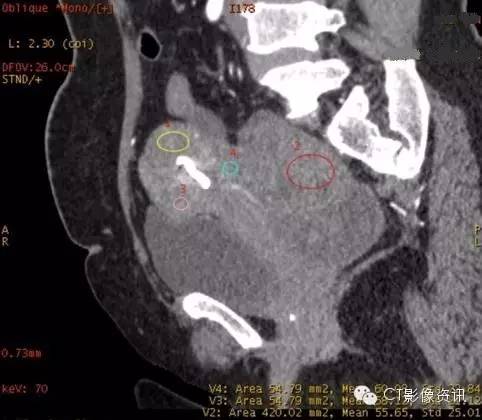

病史 女,52岁,下腹部坠胀半年 查体中下腹部触及包块 5年前曾行子宫肌瘤手术切除

1、CT表现 2、常规CT诊断 结合病史,实性病变考虑子宫肌瘤复发 囊实性病变性质待定,子宫肌瘤复发?卵巢病变?

3、能谱曲线分析